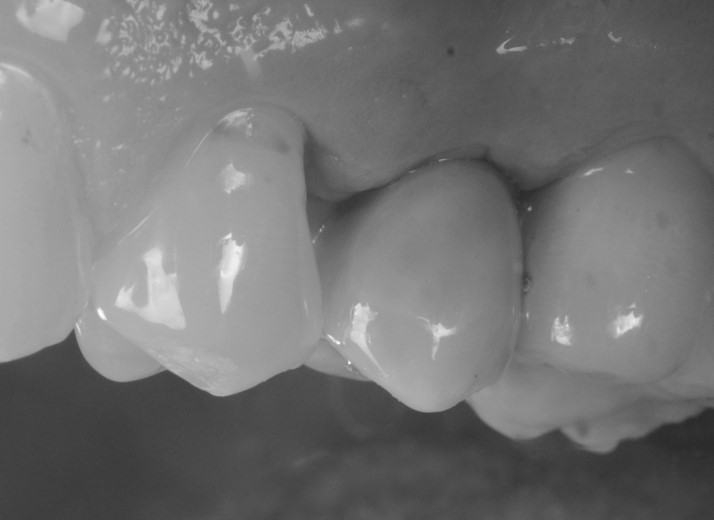

Il materiale prescelto per la stampa era un composito ibrido, caricato con ceramica, certificato per la stampa di restauri definitivi (Fig. 14). Il moncone individuale, fresato a 5 assi in titanio (TQM®, Gioia del Colle, Bari, Italia) veniva avvitato in bocca (Fig. 15,16) dopo rimozione della vite di guarigione; successivamente si applicava la corona definitiva (Fig. 17,18).

Consegna del restauro, visione laterale

Fig. 17. Consegna del restauro, visione laterale.

Consegna del restauro, visione occlusale

Fig. 18. Consegna del restauro, visione occlusale.